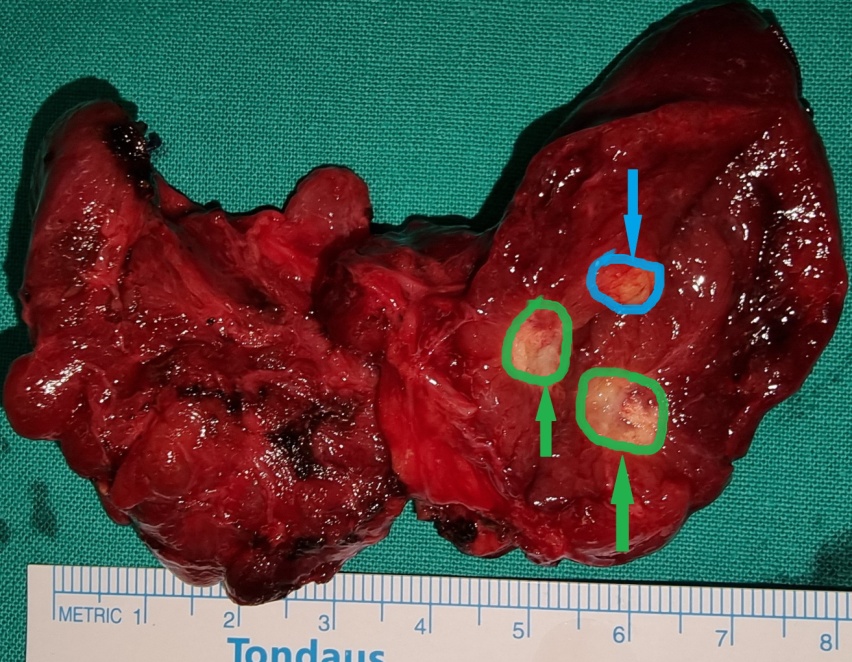

Blue arrow — Parathyroid adenoma. Green arrow — Area of necrosis and hemorrhage (Courtesy Dr. V. Penopoulos)

Cross section of the surgical specimen. Areas of necrosis are evident (Courtesy Dr. V. Penopoulos)